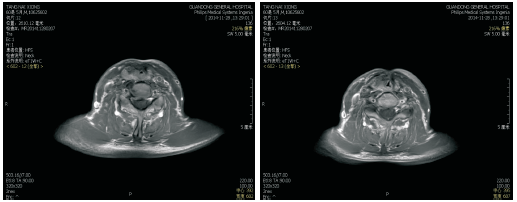

2012-05-18喉部增强CT:喉癌术后, 左侧舌骨术后改变, 与2010-12-28 CT对照, 原左侧声带小结节消失, 新增左侧声带中部小结节, 见图2和图3。诊断:左侧声门型鳞状细胞癌术后局部复发rT2N0M0 Ⅱ 期, 无病生存期17个月, 建议进一步检查。